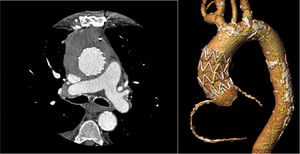

The surgery was performed without complications and the patient was discharged on oral linezolid. A year and a half later, computed tomography showed the endograft was correctly positioned and pseudoaneurysm was excluded (figure 2). Blood inflammatory markers were minimally elevated. The sternal wound remained closed, with no signs of skin inflammation.